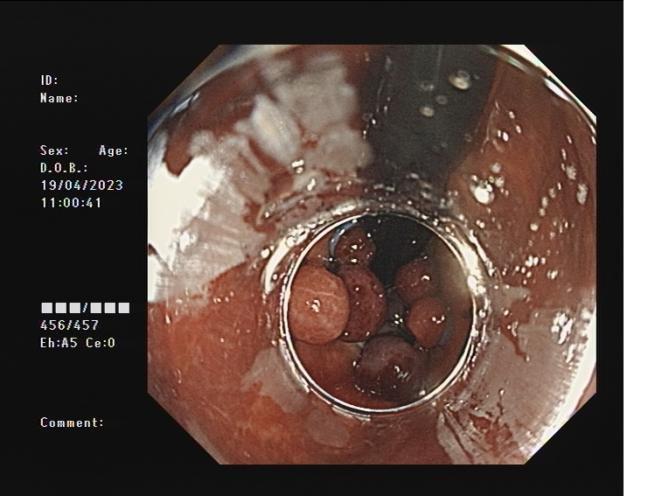

內痔 內鏡下套扎術

內鏡下內痔套扎術:治療內痔并脫出和(或)出血等癥狀,包括II、Ⅲ度內痔等。